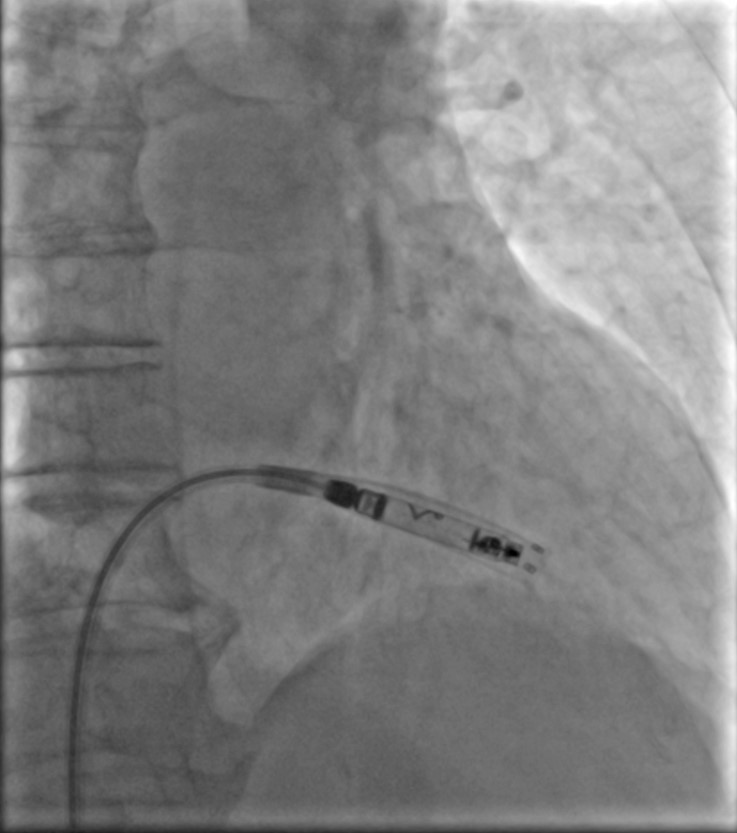

W Pracowni Elektroterapii Kaszubskiego Centrum Chorób Serca i Naczyń w szpitalu Wejherowie, wykonano pierwsze zabiegi implantacji nowego, bezelektrodowego systemu stymulacji serca. Jest to niewielkie urządzenie, wielkości kapsułki leku, pozbawione elektrod, które wszczepia się bezpośrednio do wnętrza prawego przedsionka i/lub prawej komory serca.

Zabieg wykonano na początku kwietnia 2025 roku. Jak wyjaśnia kierownik Pracowni Elektroterapii, dr Roman Moroz "to system nowy, o aktywnej, spiralnej fiksacji, pozwalający na skuteczną stymulację dwujamową z zachowaną pełną synchronią przedsionkowo-komorową".

fot. Szpitale Pomorskie